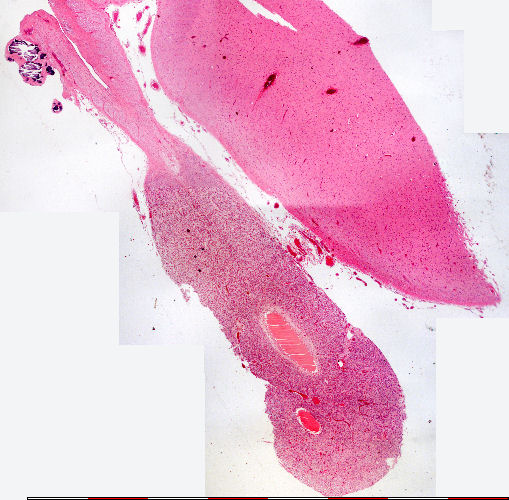

Pineaal klier: Baie lae vergroting

Pineal gland: Very low magnification